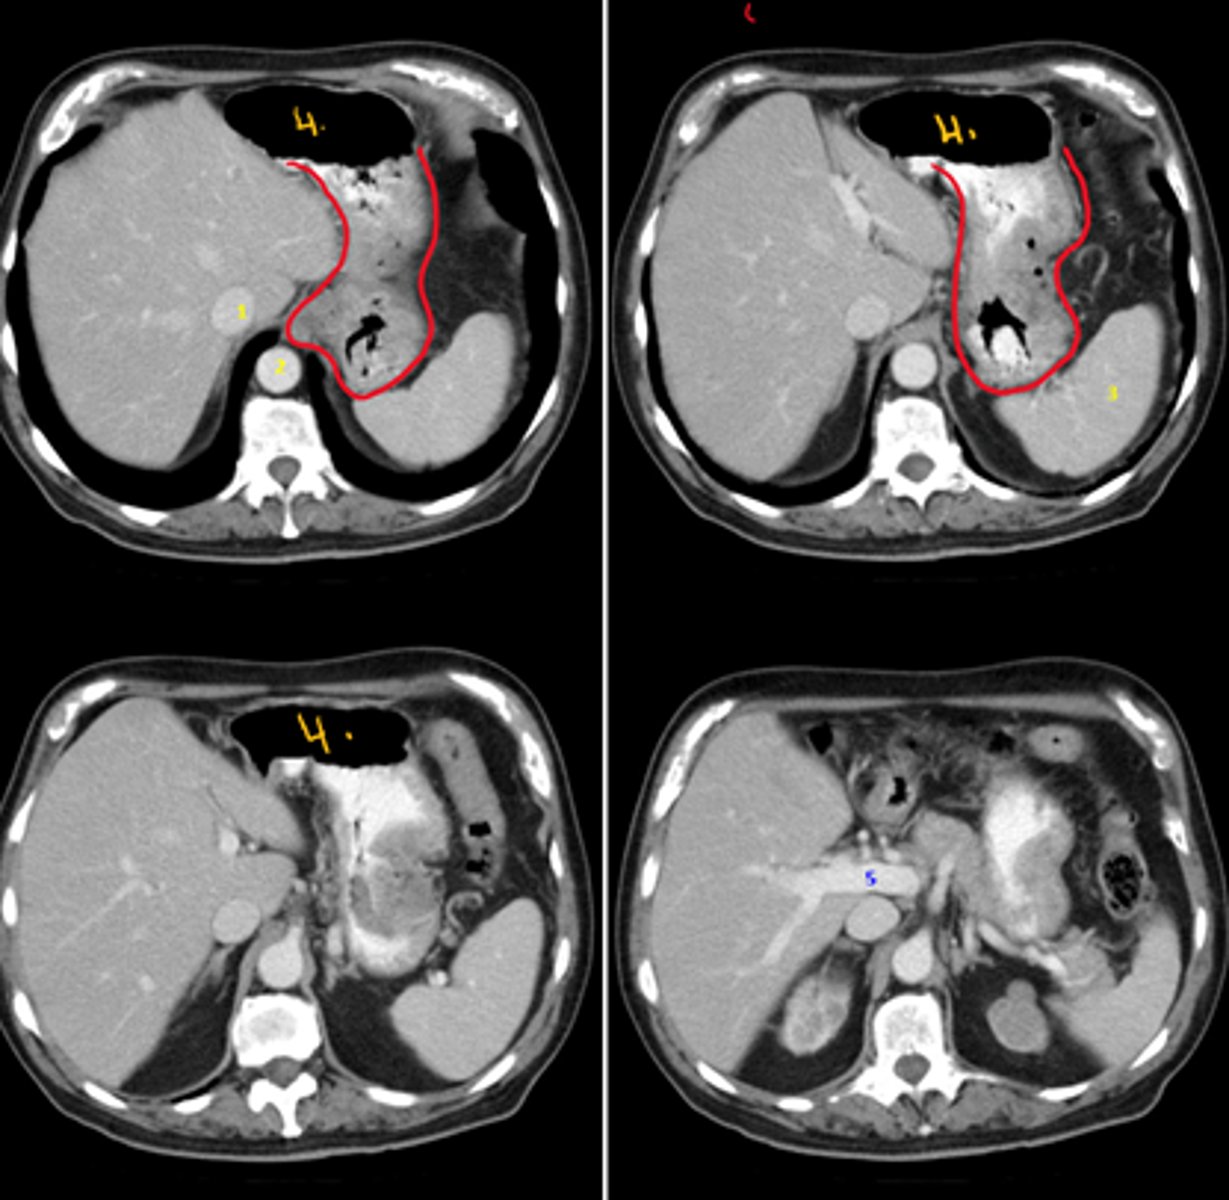

Idedntify the indicated structures on the following radiograph

1. IVC

2. Descending Aorta

3. Spleen

4. Stomach

5. Portal vein (bigger than proper hepatic artery)

growth shown in red: gastric cancer

<p>1. IVC</p><p>2. Descending Aorta</p><p>3. Spleen</p><p>4. Stomach</p><p>5. Portal vein (bigger than proper hepatic artery)</p><p>growth shown in red: gastric cancer</p>

What structures are at risk of spread of the following growth?

Structures it will spread: celiac lymph nodes to liver, local to liver and spleen, venous drainage to liver (thus the liver has two methods of spread from the stomach)

gastric cancer

<p>Structures it will spread: celiac lymph nodes to liver, local to liver and spleen, venous drainage to liver (thus the liver has two methods of spread from the stomach)</p><p>gastric cancer</p>